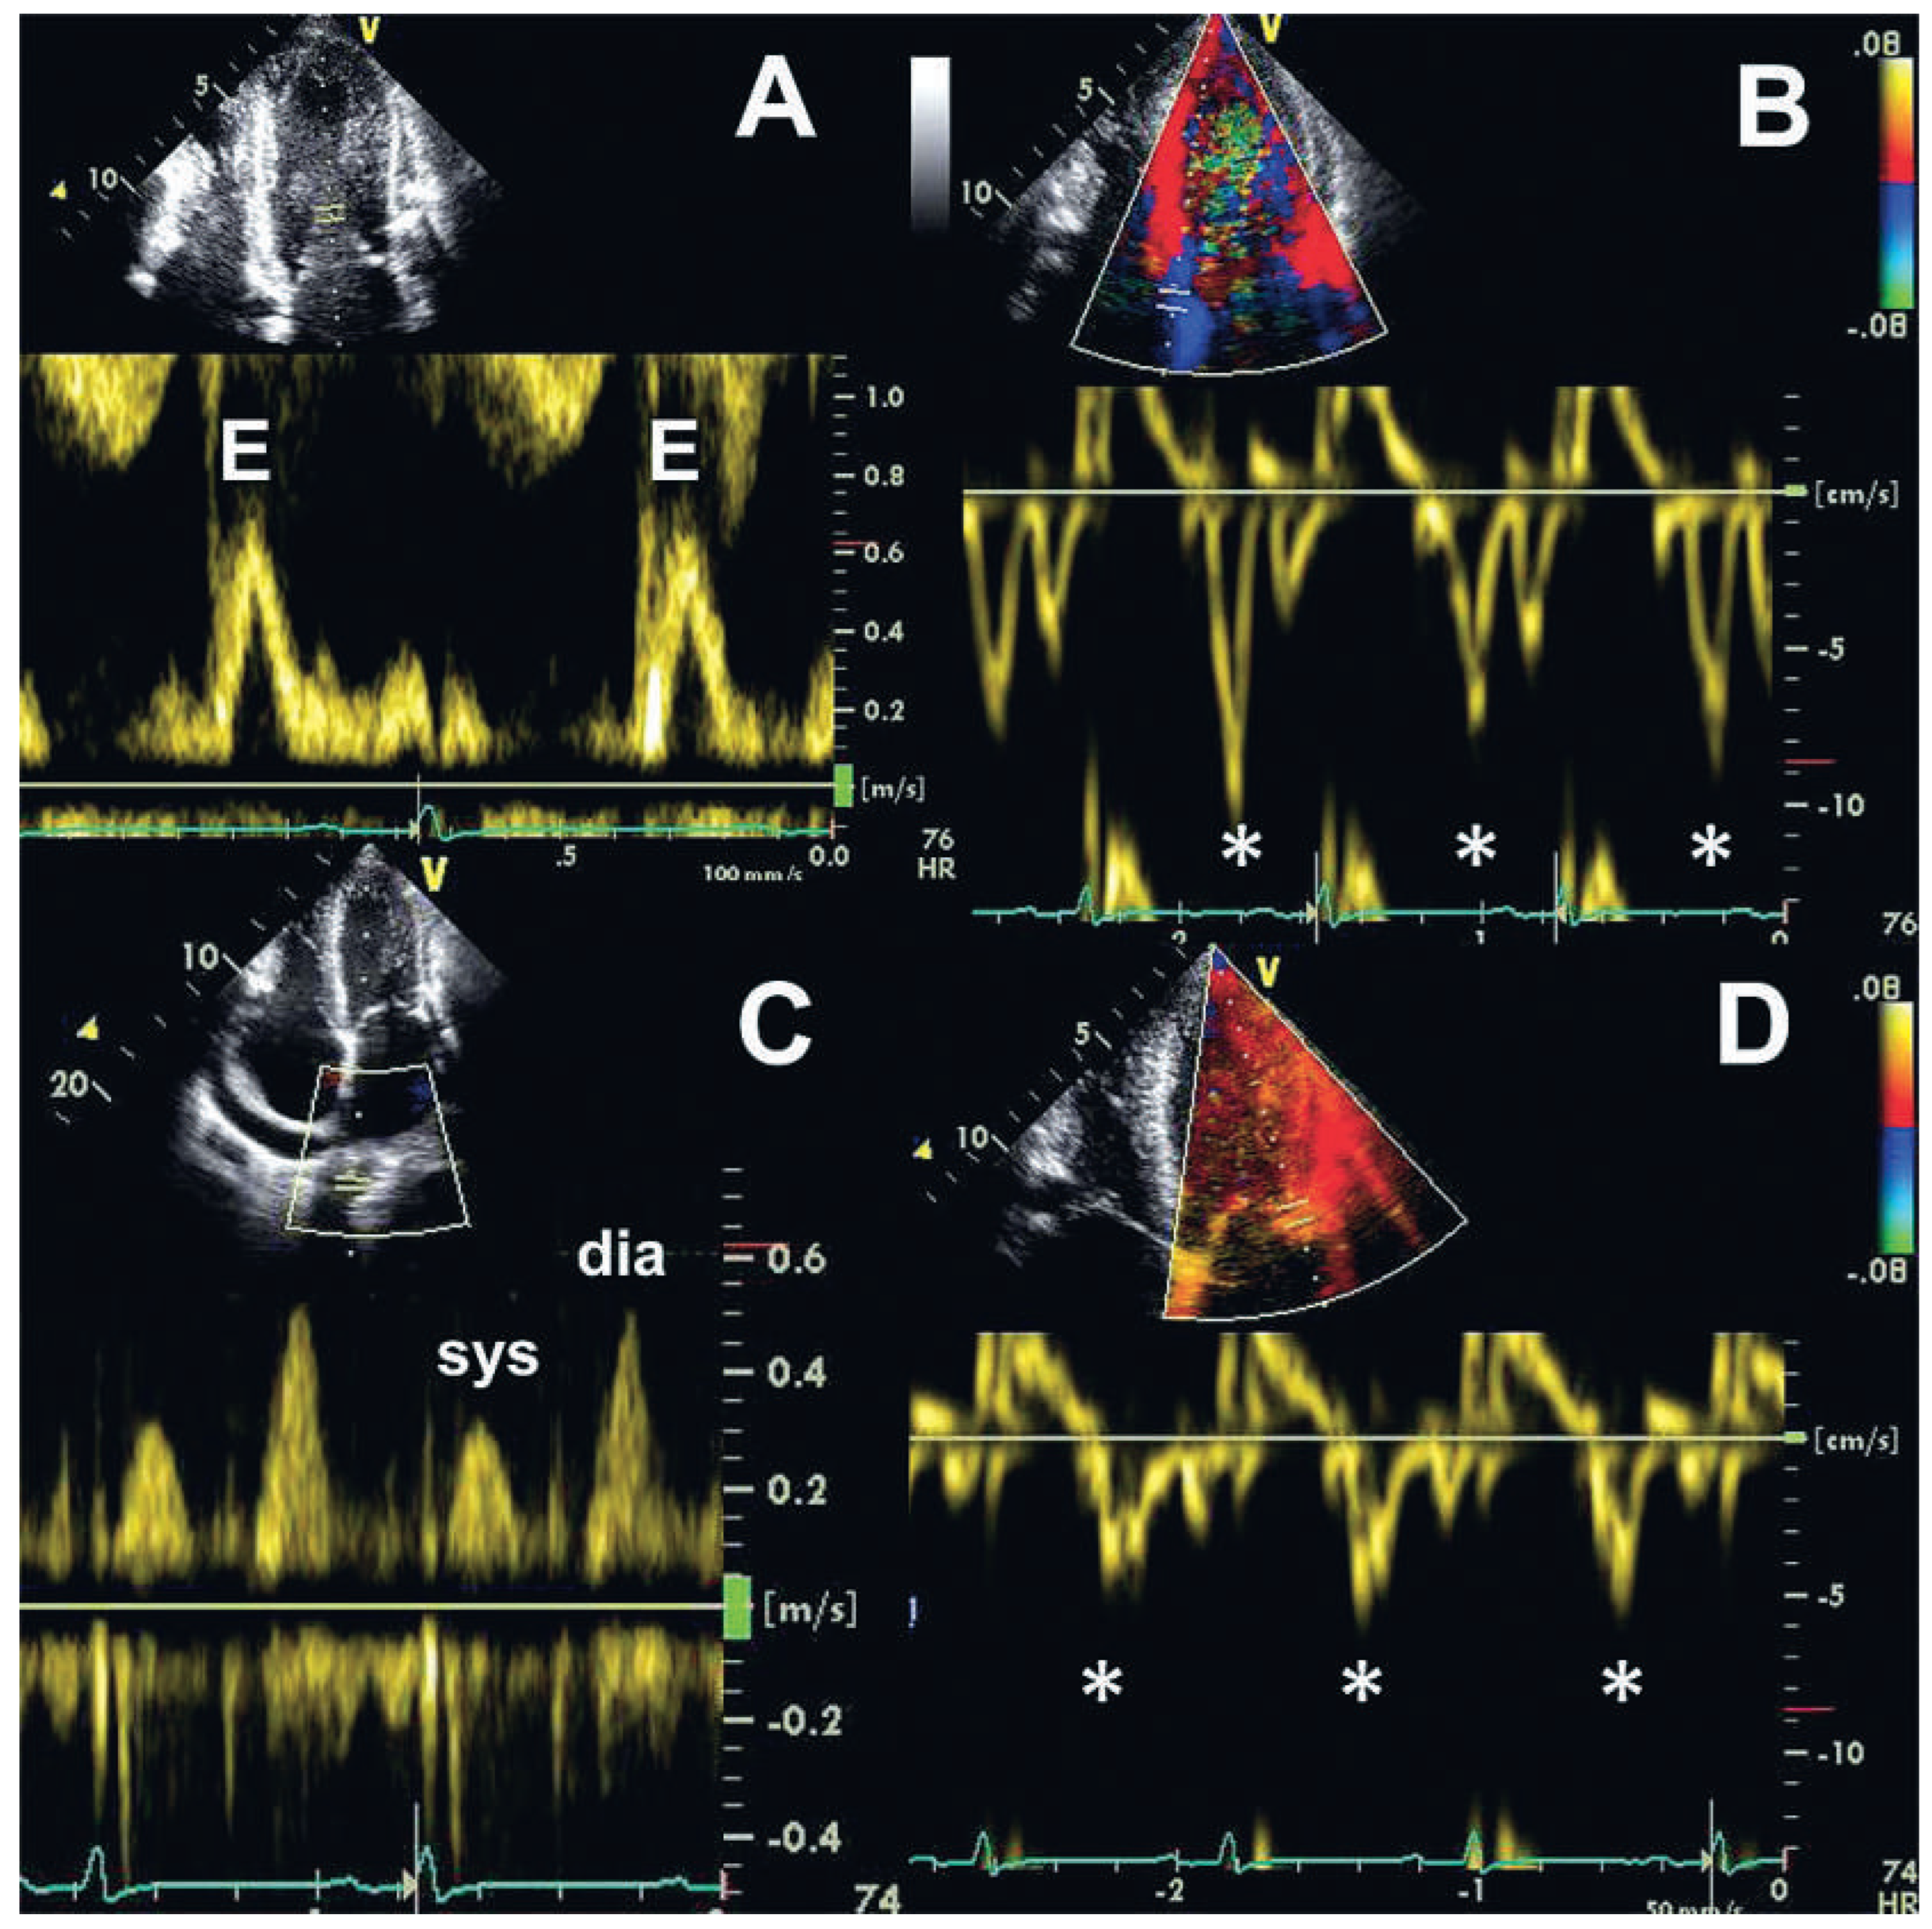

A 56-year-old man was admitted with massive signs of right heart failure, which had evolved over weeks. Chest X-ray revealed extensive pericardial calcifications in the lateral view ( Figure 1). Transthoracic echocardiography showed only mildly impaired biventricular systolic function but a dilated inferior vena cava without respiratory variability. The peak early mitral annular velocities (e’) assessed by pulsed wave tissue Doppler at the septal and lateral mitral annulus were 8 and 6 cm/s, and the ratio of the peak early transmitral velocity (E) to e’ (E/e’), based on an average e’ of 7 cm/s, was only 10 (Figure 2A,B,D). The pulmonary venous flow was clearly abnormal however (Figure 2C). There was an exaggerated respiratory variability of mitral in-flow (Figure 3).

Figure 2. Transthoracic Doppler echocardiography. (A) Transmitral inflow assessed by pulsed wave Doppler (peak early transmitral velocity [E], 0.7 m/s). (B,D) Pulsed wave tissue Doppler at the septal (B) and lateral (D) mitral annulus revealing preserved peak early mitral annular velocities (e’, asterisks; septal 8 cm/s, lateral 6 cm/s). (C) Pulmonary venous flow assessed by pulsed wave Doppler showing prominent diastolic flow. dia = diastolic; sys = systolic.